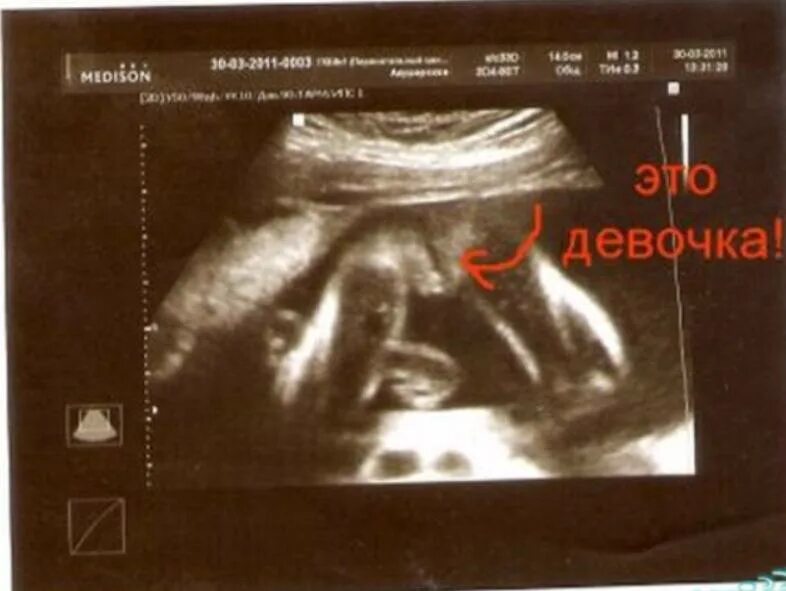

Узи определение пола ошибки